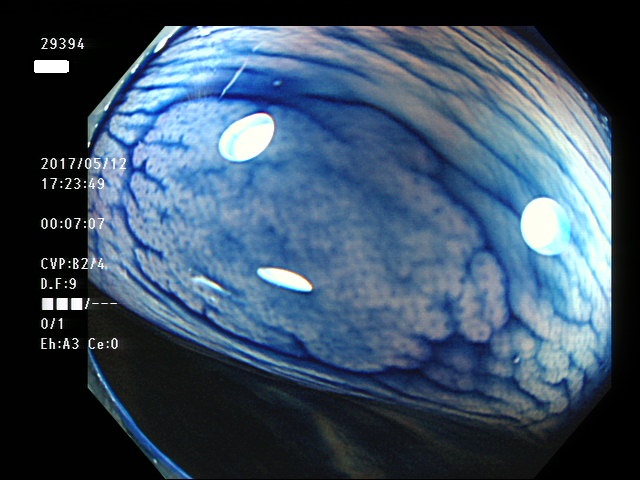

過形成ポリープの重要な特徴は「平坦で正常粘膜と区別がつきにくく、腺腫と比較して非常に見落としが多い」ということです。正確な統計は無いのですが「過形成の見落とし」は「腺腫の見落とし」の10倍以上の頻度と予測します。

左側に小型の過形成が数十、多発する。個々の過形成が直接、癌化するリスクは低いが、腸全体が腫瘍が出来易い体質であることが多く、腺腫および腺腫由来の癌が出来易い。また遺伝的にDNA修復機能の低下が見つかることもある(文献